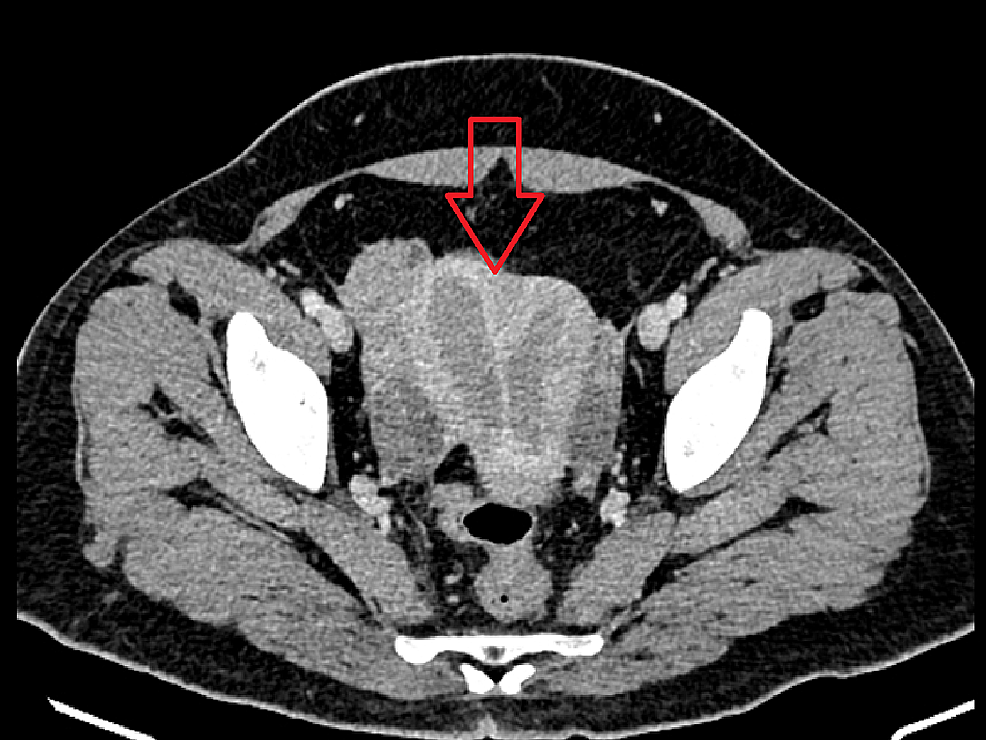

Ct Simulation For Endometrial Cancer . Clinical practice guidelines recommend against routine preoperative axial imaging studies (ct/mri) for endometrial cancer, except for cases of locally advanced disease or. Endometrial carcinoma staging allows appropriate treatment options to be considered and enables greater prognostic accuracy for endometrial carcinoma. Upfront radiation therapy consisting of brachytherapy with or without external beam radiation therapy is considered standard of care for patients with endometrial carcinoma who. Patients undergo office pipelle biopsy or examination under anesthesia and d&c to obtain endometrial tissue samples. With the results of several recently published clinical trials, this guideline informs on the use of adjuvant radiation therapy (rt) and systemic therapy in the. Ct findings in two different patients with endometrial cancer.

Endometrial carcinoma staging allows appropriate treatment options to be considered and enables greater prognostic accuracy for endometrial carcinoma. Upfront radiation therapy consisting of brachytherapy with or without external beam radiation therapy is considered standard of care for patients with endometrial carcinoma who. With the results of several recently published clinical trials, this guideline informs on the use of adjuvant radiation therapy (rt) and systemic therapy in the. Patients undergo office pipelle biopsy or examination under anesthesia and d&c to obtain endometrial tissue samples. Clinical practice guidelines recommend against routine preoperative axial imaging studies (ct/mri) for endometrial cancer, except for cases of locally advanced disease or. Ct findings in two different patients with endometrial cancer.